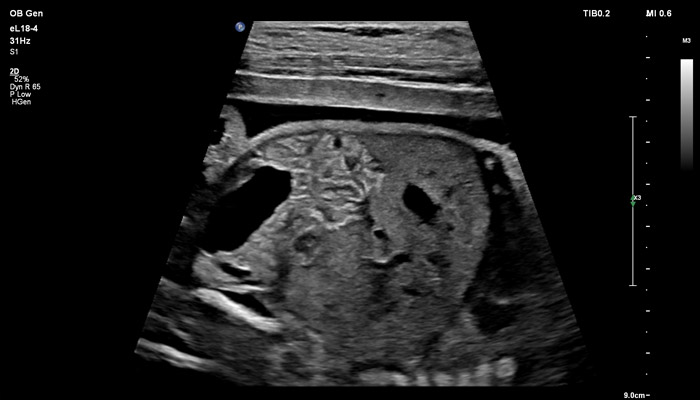

Линейный матричный датчик eL18-4 позволяет получить детальную информацию об анатомии плода и выявить пороки на ранней стадии развития. Сверхширокополосная PureWave матрица датчика генерирует частоты в диапазоне 2-22 МГц, что формирует одинаково высокоинформативные, четкие изображения по всей глубине сканирования до 14 см.

Высокочастотный датчик Philips eL18-4 содержит решетку из 1920 активных монокристаллических пьезоэлементов, выполненных по усовершенствованной технологии PureWave. Это обеспечивает высокодетальную 2D визуализацию, которая в совокупности с глубиной сканирования необходима для уверенной диагностики в акушерстве.

До введения высокочастотных линейных датчиков точная ультразвуковая диагностика мочевой системы плода была доступна в основном после 16-17 недель беременности. Новая технология еL18-4 позволяет проводить раннюю морфологическую оценку плода уже в первом триместре. Клинический случай с применением eL18-4 демонстрирует, что кортико-медуллярная дифференцировка почек плода возможна на 14 неделе беременности”.

В случае аномалий позвоночника, оценка ануса важна, чтобы исключить аноректальные пороки развития, которые могут быть частью более широкой группы аномалий, известных как VACTERL (аномалии позвоночника, атрезия ануса, пороки сердца, трахеопищеводный свищ, аномалии почек, дефекты лучевой кости). Исследования в США показали, что очень высокое качество изображений еL18-4 повышают уверенность клиницистов в исключении аноректальной аномалии плода.

Использование линейного матричного датчика eL18-4 при осмотре беременных в I триместре, особенно на ранних сроках, позволяет ограничиться трансабдоминальным сканированием вместо трансвагинального и при этом получить максимально полную диагностическую информацию. Отсутствие полостного исследования чрезвычайно важно для соблюдения принципа ALARA – использования минимальной необходимой мощности для безопасности пациента. Благодаря применению мультичастотного датчика с диапазоном от 2 до 22 МГц через переднюю брюшную стенку хорошо определяется эмбрион длиной 3 мм, что соответствует шестой неделе беременности. В конце I триместра с eL18-4 достаточно отчётливо визуализируется четырёхкамерный срез сердца, мочевой пузырь и сосуды пуповины, которые, как правило, определяются только при трансвагинальном сканировании.

Во II триместре беременности высокая разрешающая способность eL18-4 позволяет детально изучить структуру органов и тканей и увидеть многие нюансы, которые при работе другими датчиками не обнаруживались или становились очевидны в более поздние сроки. Например, у 19-недельного плода визуализируется перегородка носа, мышцы языка, диафрагма между грудной и брюшной полостью, на 20-й неделе чётко определяются оболочки спинного мозга и уретра, а на 24-й – хорошо дифференцируются корень лёгкого, борозды и извилины мозжечка и многие другие структуры.